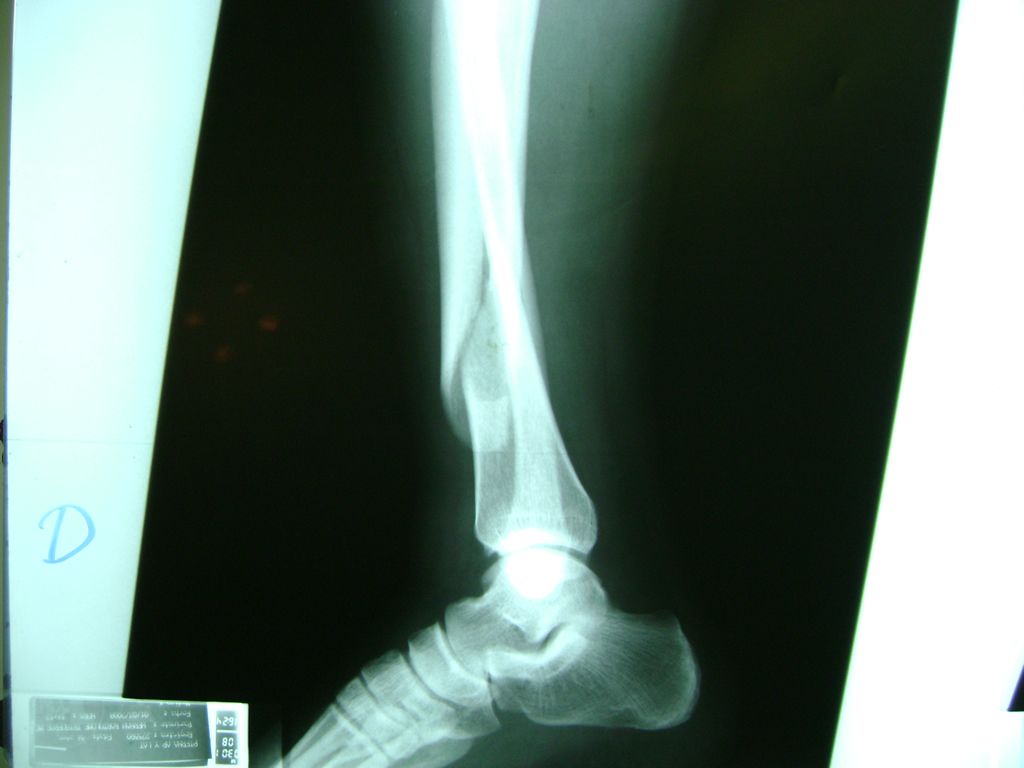

La mayor parte de las roturas implican a la parte proximal del hueso (parte del hueso próximo a la rodilla) o a la parte distal (parte del hueso cerca del tobillo).

Debido a la fina cobertura de piel que recubre la tibia y el peroné, las fracturas generalmente son abiertas, es decir, el hueso roto rasga la piel, atravesándola. Las fracturas de tibia y peroné generalmente se producen por un fuerte impacto o torsión.